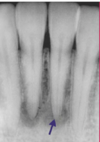

What is the radiographic finding?

Residual Cyst